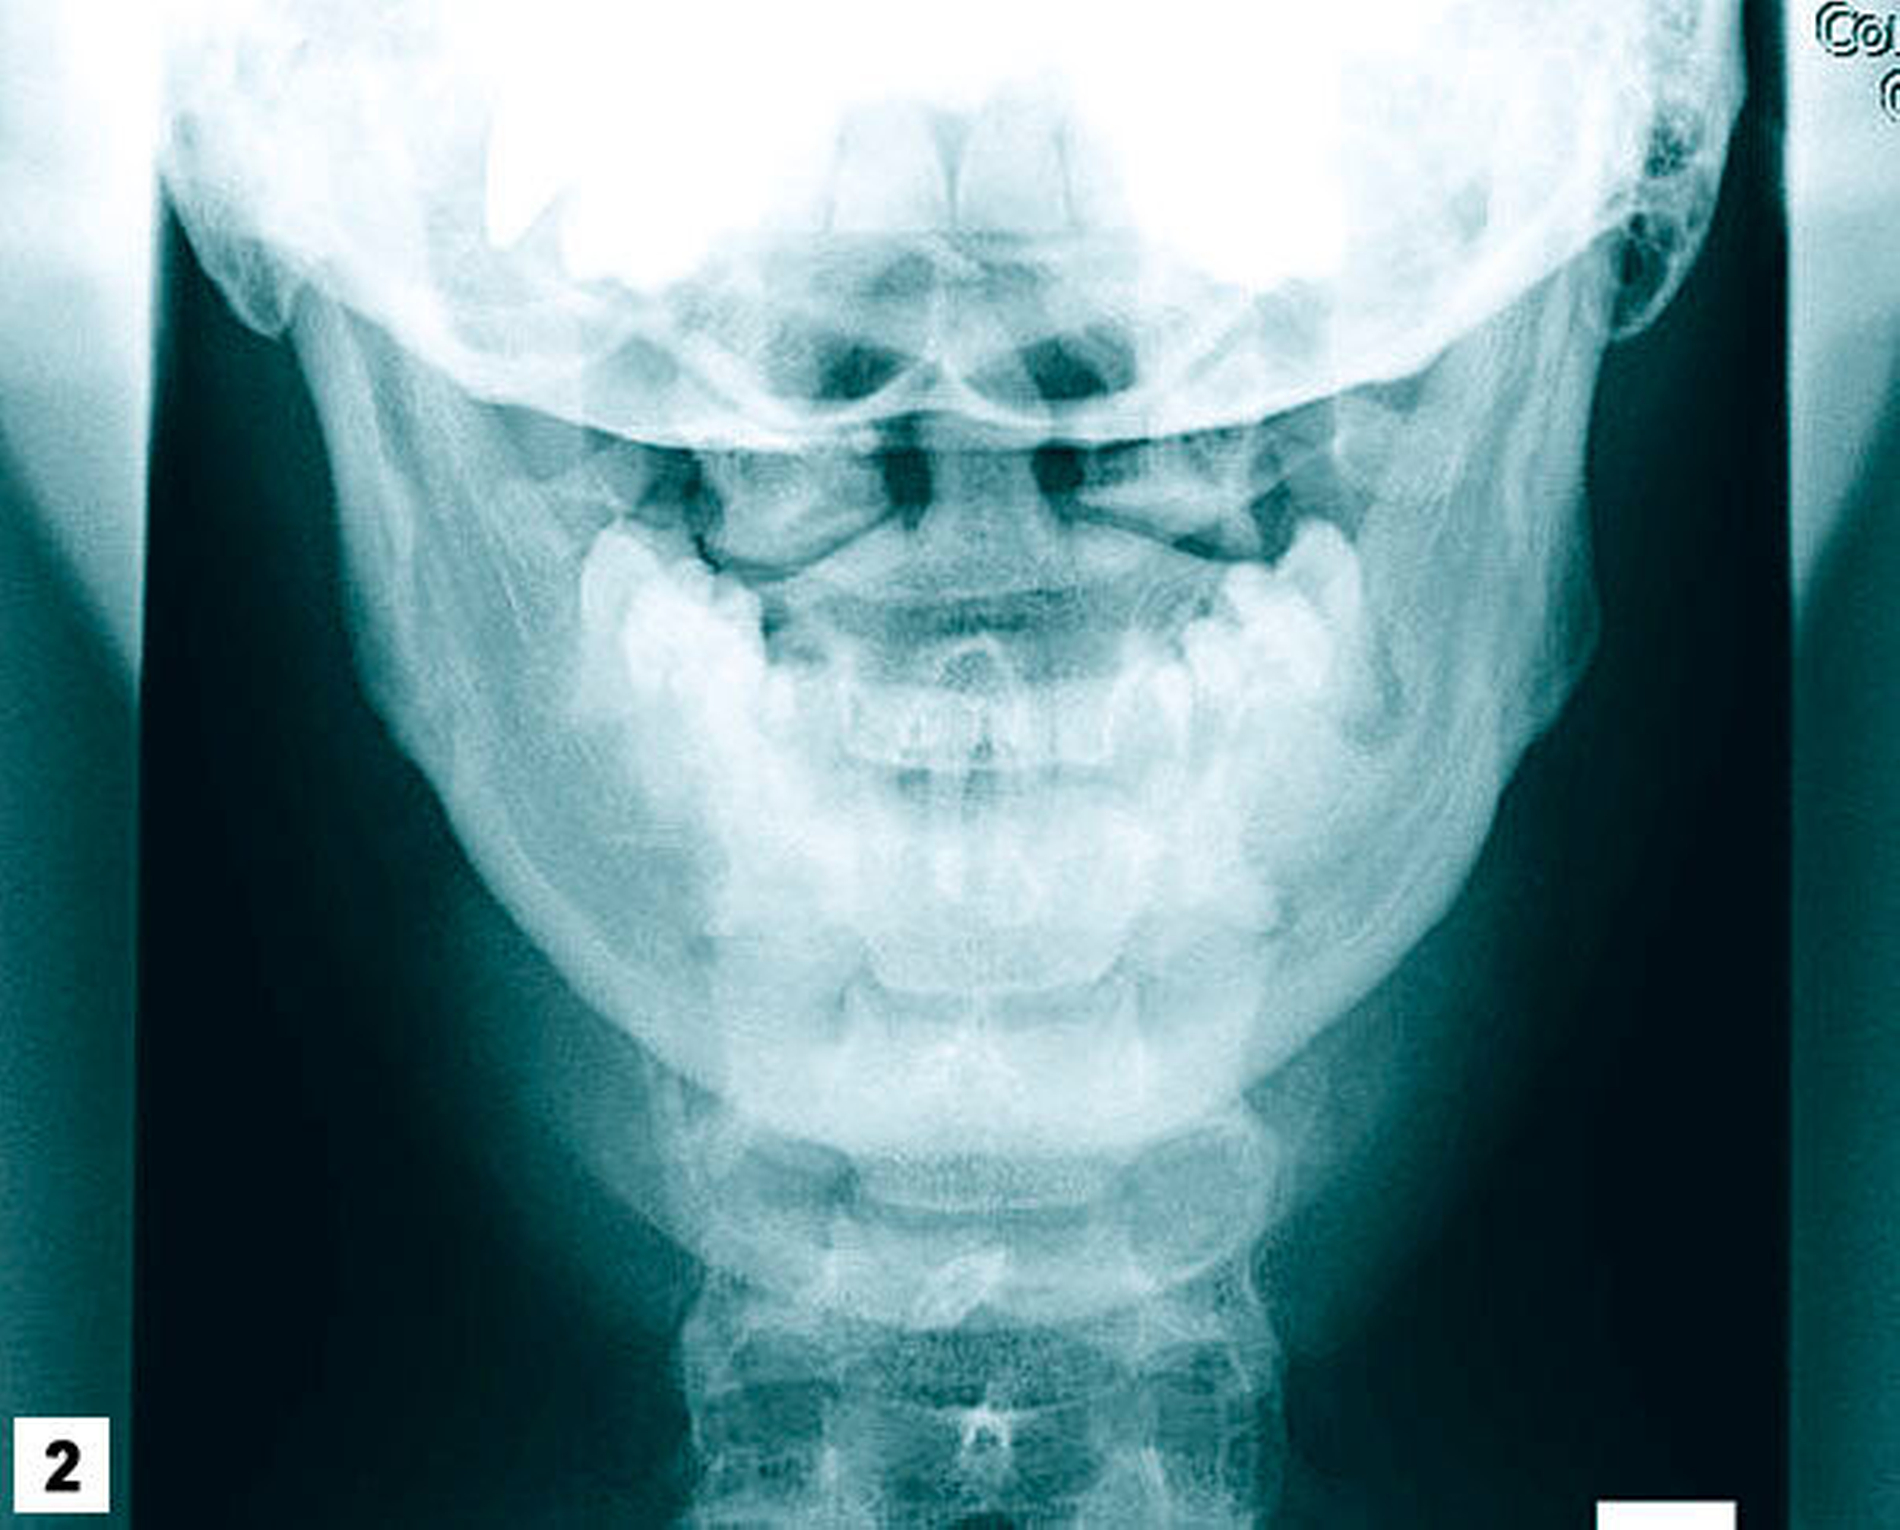

Der Patient ist afghanischer Herkunft, war (soweit bekannt) gesund und in gutem Allgemein- und Ernährungszustand. Klinisch zeigten sich eine Dichromatie und eine leichte Lidspaltenöffnungsdifferenz (Abbildung 1). Die intraorale Inspektion war weitgehend unauffällig. Die von der Chirurgin mitgelieferten Nativröntgenbilder ließen eine apikale Osteolyse in der Region des Zahnes 37 vermuten, zudem zeigte sich ein metalldichter Fremdkörper mit Projektion auf die Kieferhöhle rechts (Abbildungen 2 und 3).